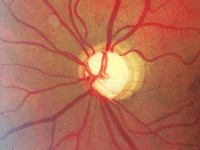

Media opacity: Cloudiness in the normally clear parts of the eye

The 2 parts of the eye responsible for focusing light are the cornea and the lens.

In some children, either the cornea or the lens can become cloudy and cause less light to be able to reach the back of the eye.